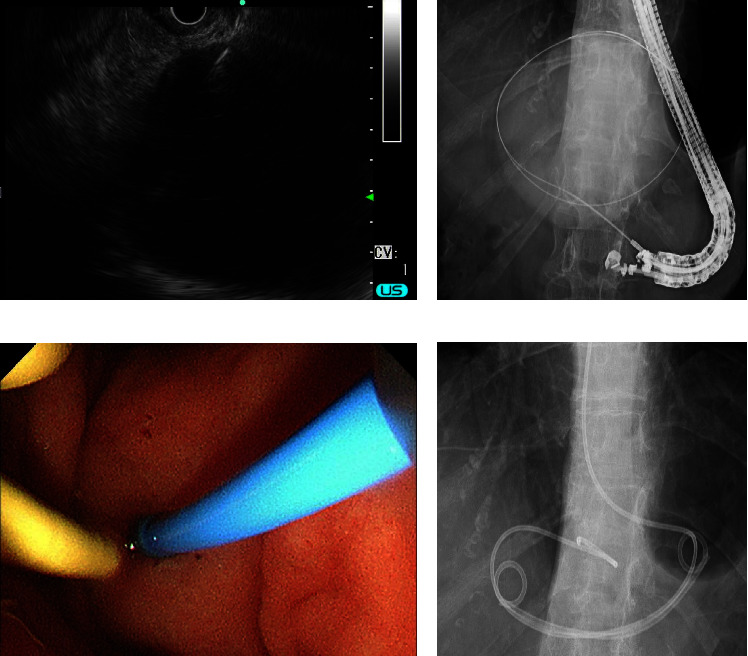

A liver cyst is hepatic fluid-filled cavities often detected in clinical surveillances such as a health examination. Although the liver cyst is usually asymptomatic and observed without any therapeutic intervention, it can be symptomatic and needs treatment due to its enlargement, hemorrhage, and infection. A 74-year-old woman presented with upper abdominal pain and a huge liver cyst in the left lobe. Several examinations including image findings revealed that the symptom could be derived from the liver cyst. Although there is no definite guideline of treatment for symptomatic liver cysts, percutaneous ultrasound-guided drainage with sclerotherapy or surgery is often selected. Because of anatomical accessibility to the liver cyst and the patient's wish, we performed endoscopic transgastric drainage with insertion of both an internal stent and an external nasocystic tube. Sclerotherapy with minocycline hydrochloride was performed through the nasocystic tube, and the liver cyst shrunk completely without any complications. This is the first reported method of administering minocycline hydrochloride through a nasocystic tube, which can be a therapeutic option for patients with symptomatic liver cysts.

Abstract Image